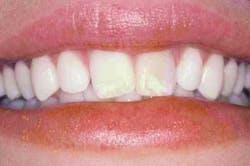

A 26-year-old female wanted a beautiful smile in time for her upcoming wedding. Tooth No. 9 (Figure 1), had been traumatized early in life and treated with root-canal therapy. It was now darkly discolored. The two centrals had large, unsightly white demineralization marks and were misaligned, mainly due to a space and size discrepancy. The short lengths of the two laterals accentuated the skinny, "rabbit-shaped" appearance of the central incisors, increasing the illusion of their incisal thirds being the same width as the gingival third. Furthermore, due to the malalignment and shape, the gumline was uneven with inflamed interproximal gingiva.